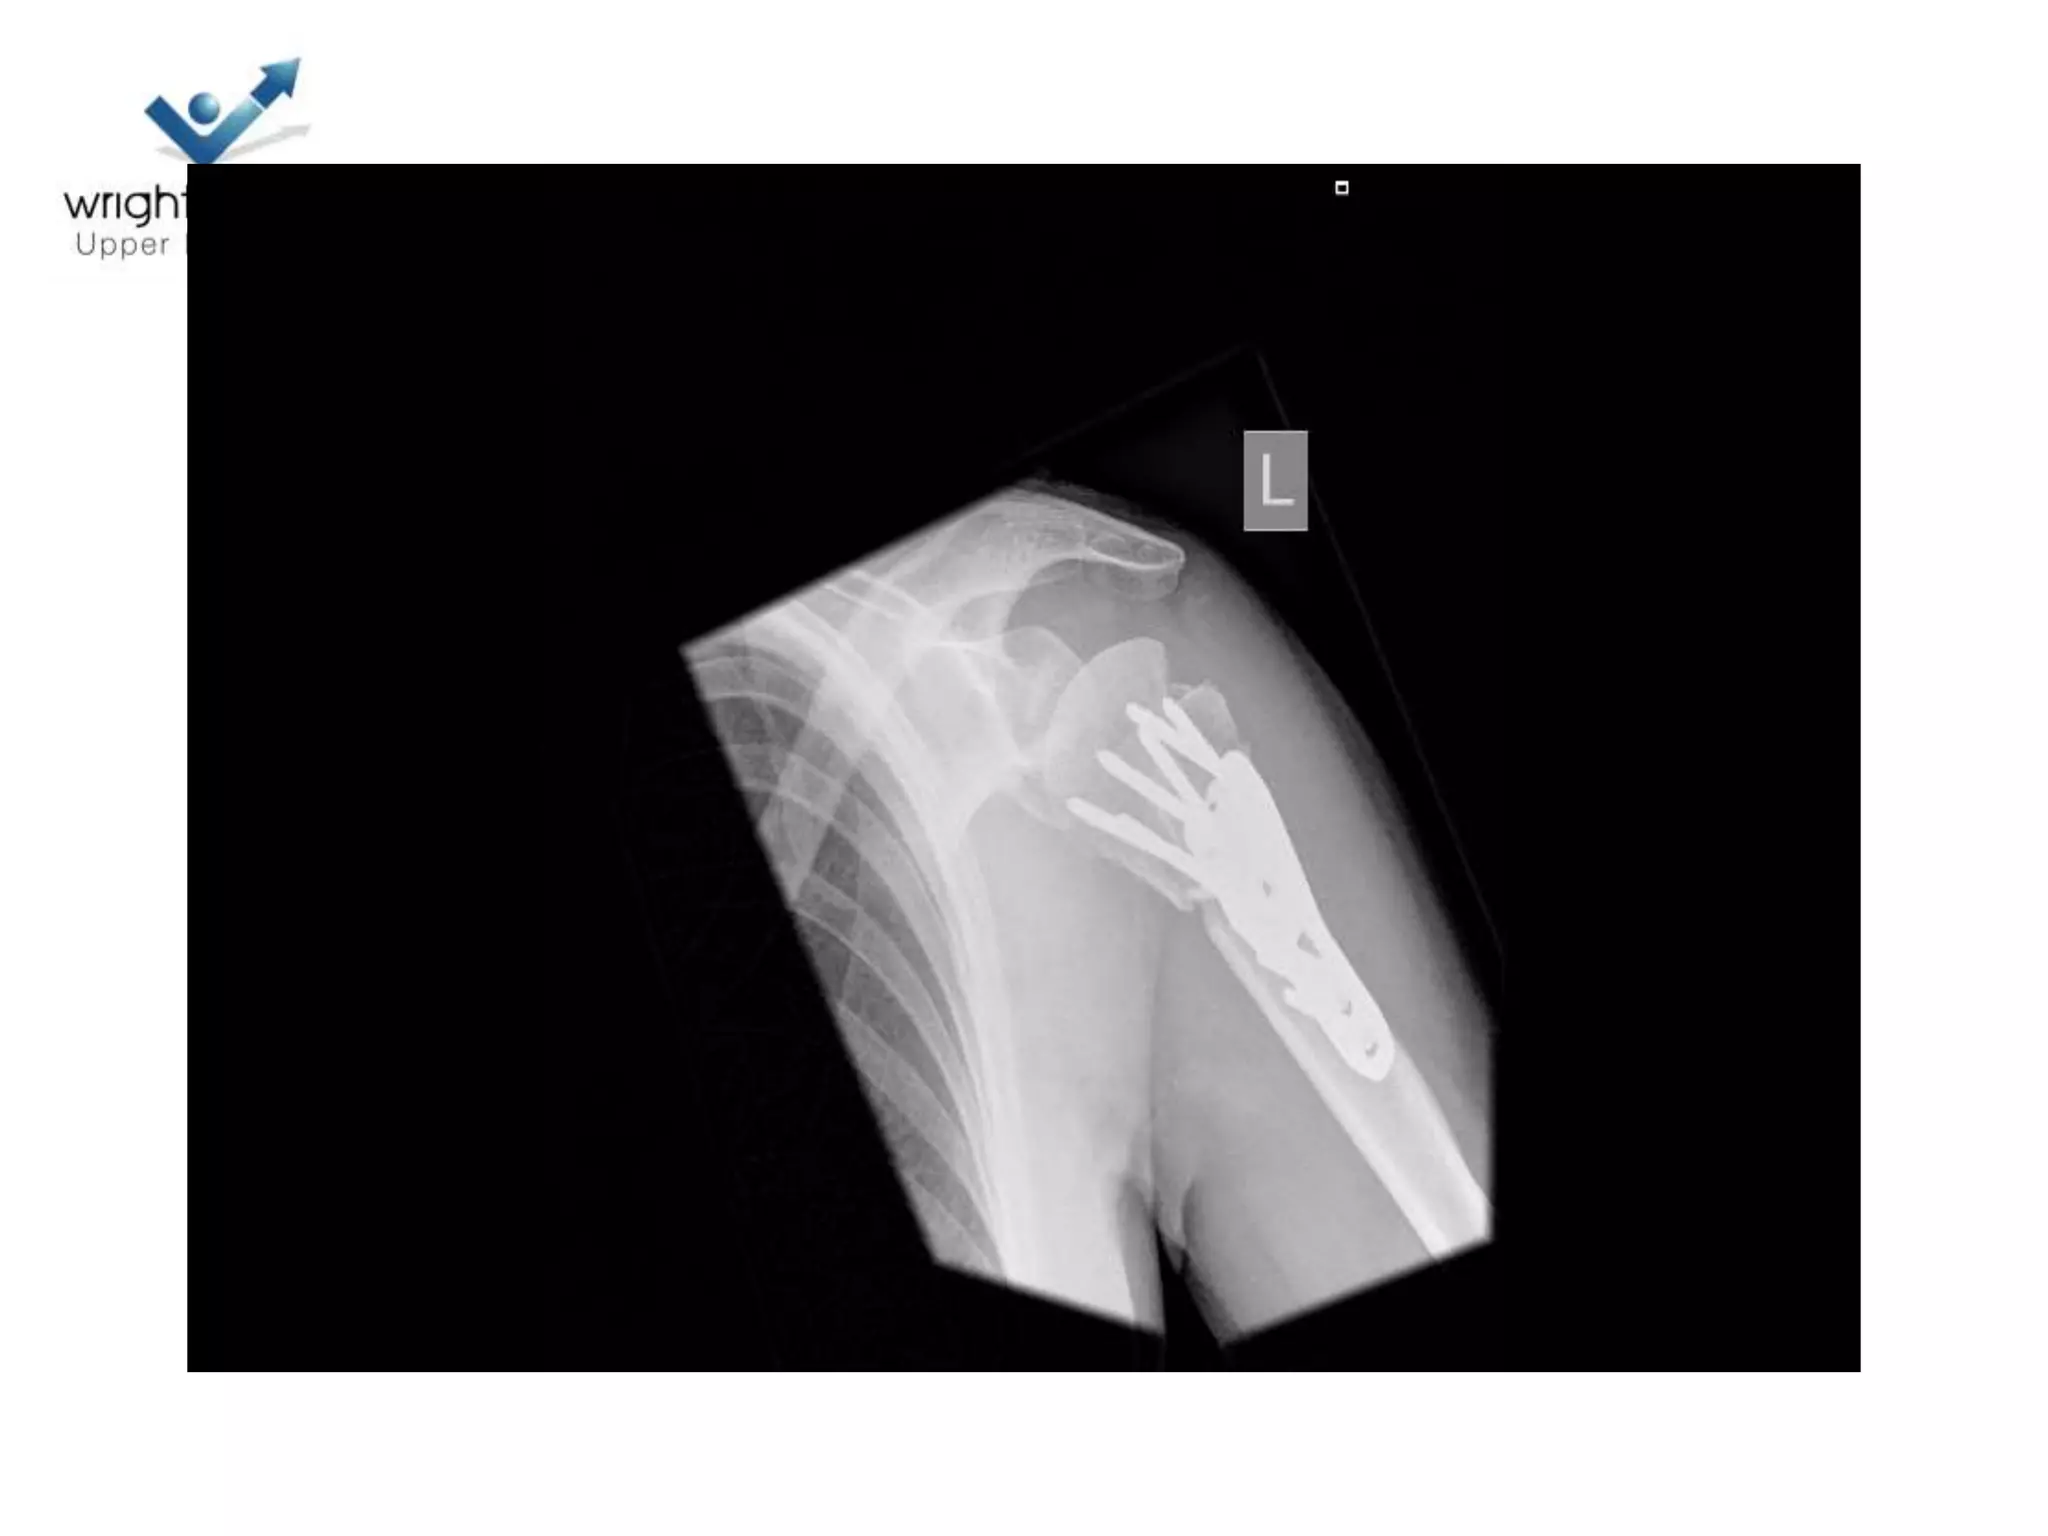

Locking plate; Tips

Locking plates: Tips

Locking plate: Tips

4 Next…